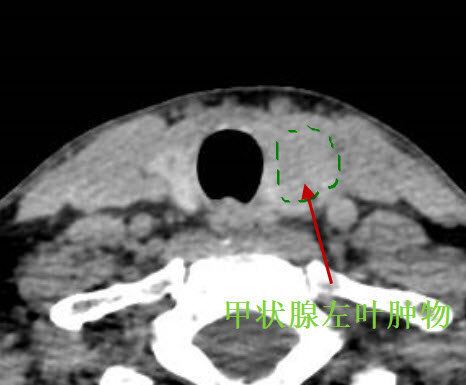

對(duì)于甲狀腺腫物,一般比較大的,采用手術(shù)切除。目前手術(shù)切除的技術(shù)以小切口微創(chuàng)手術(shù)為主,傳統(tǒng)的大切口甲狀腺手術(shù)由于不美觀做的越來越少了。最近有一個(gè)甲狀腺較大腫物的患者,找耳鼻喉鄭立崗醫(yī)生做了小切口甲狀腺腫物切除的手術(shù)?;颊哧悾?,42歲,廣東佛山人。患者1周前刷牙時(shí)無意中發(fā)現(xiàn)左側(cè)頸部腫物,腫物逐漸增大,偶伴有脹痛感,遂到我院門診查頸部CT示甲狀腺左側(cè)葉下極腫塊。為進(jìn)一步診治,門診擬頸部外表面腫物收住我科。患者術(shù)前檢查腫物直徑約3cm,比較大。這次做了一個(gè)4cm的小切口,逐層的暴露甲狀腺及腫物后切除腫物,術(shù)中注意保護(hù)喉返神經(jīng),完整切除腫物后縫合切口。整個(gè)的手術(shù)用時(shí)約1小時(shí),非常的順利。術(shù)后查房患者無明顯的不適,無手術(shù)相關(guān)的并發(fā)癥。對(duì)于甲狀腺腫物,小切口微創(chuàng)手術(shù)相對(duì)比較簡(jiǎn)單,并發(fā)癥少。是一個(gè)比較好的選擇。如果您還有什么問題,歡迎留言和耳鼻喉鄭立崗醫(yī)生進(jìn)一步交流。